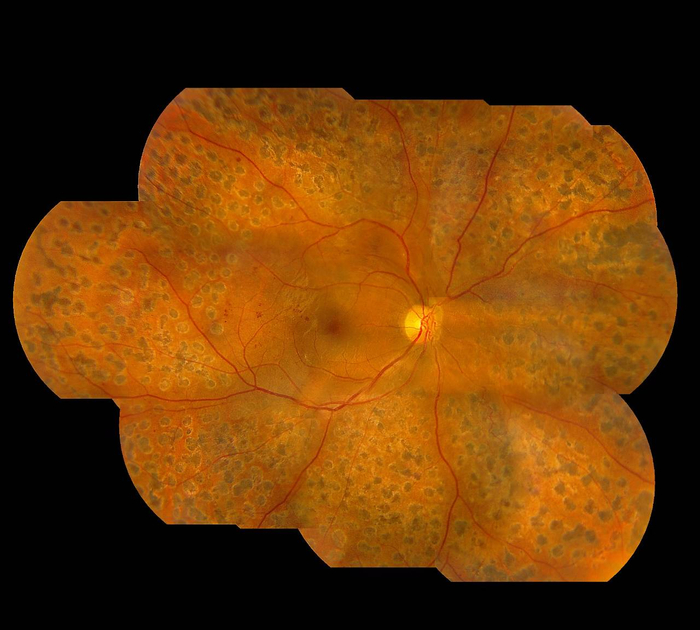

图2:经过玻璃体切除手术及激光治疗后的眼底照,可见出血得以治愈以及视网膜复位

林顺潮指出,局部激光治疗、玻璃体内注射药物或复合治疗,都是糖尿病视网膜病变的主要治疗方式。如能早期发现并进行针对性治疗,病人的视力大多数可以保留。然而如果耽误病情,导致视网膜脱落时间过长,无法得到足够的血液供应,感光神经细胞将可能出现不可逆转的损伤。即使将视网膜复位,但病人手术后视力恢复的时间会较长,甚至可能无法恢复。